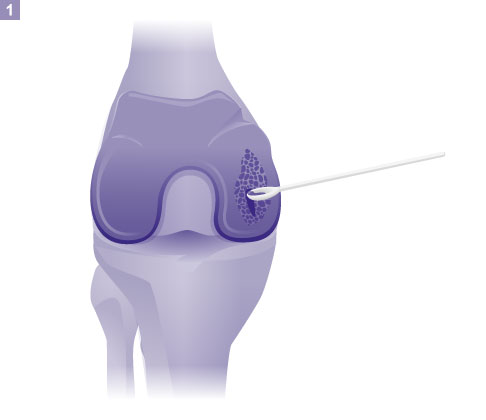

Entnahme von Knorpelgewebe, Zerkleinern zu Knorpelchips 1. Schritt: Entnahme von Knorpelgewebe, Zerkleinern zu Knorpelchips. © Gelenk-Klinik Vermischen der Knorpelchips mit körpereigenem PRP 2. Schritt: Vermischen der Knorpelchips mit körpereigenem thrombozytenreichem Plasma (PRP). © Gelenk-Klinik

Auffüllen des Defekts 3. Schritt: Auffüllen des Defekts mit dem pastenartigen Knorpelchips-PRP-Gemisch. © Gelenk-Klinik Fixieren des Knorpelimplantats mit Thrombin 4. Schritt: Fixieren des Knorpelimplantats mit Thrombin aus dem Patientenblut. © Gelenk-Klinik

Zuerst entfernt der Operateur das defekte Knorpelgewebe im Kniegelenk durch ein spezielles Instrument, das einem scharfen Löffel ähnelt. Nachdem er den geschädigten Knorpelbereich gründlich gesäubert hat, gewinnt er aus dem Randbereich des Defektes gesundes Knorpelgewebe. Dieser Knorpel wird direkt nach Entnahme zerkleinert und es entstehen die wichtigen Knorpelchips. Sie bilden die Grundbausteine für die Reparatur.